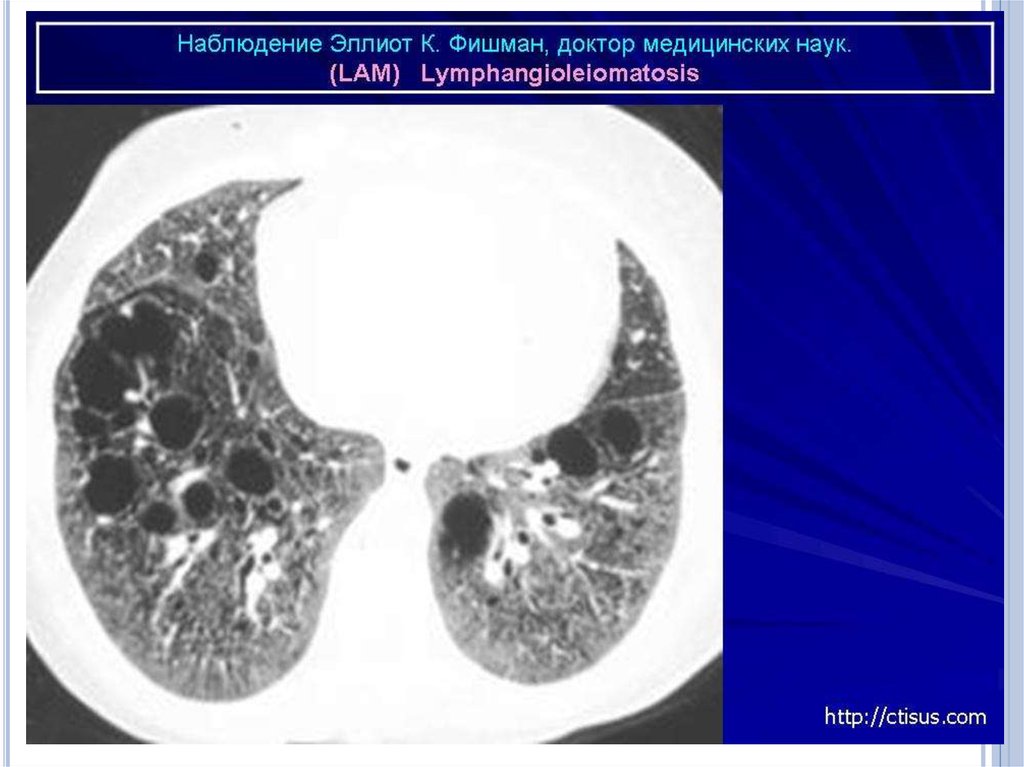

Инструментальные методы исследования

Наиболее характерный морфологический признак ЛАМ кистозная трансформация легких, которая обычно выявляется

на компьютерных томограммах. Кисты бывают двух типов:

мелкие множественные типа «сотового легкого» и

крупные кисты, присущие буллезной эмфиземе.

Толщина стенки кисты не превышает 2 мм, причем стенка

кисты выявляется не всегда и не на всем протяжении.

Окружающая легочная ткань часто не изменена. Однако

сочетание фиброзных и кистозных изменений не

противоречит диагнозу ЛАМ. Таким образом,

рентгенологическая картина ЛАМ не патогномонична.

Компьютерная томография легких. Для ЛАМ

характерны множественные диффузные, хорошо очерченные

мелкие тонкостенные кисты. Кисты при этом заболевании

значительно отличаются от зон центрилобулярной эмфиземы

легких, которые не имеют четких границ и своих собственных

стенок, а также от фиброзирующего альвеолита, при котором

основные изменения расположены по периферии легких,

имеются поля фиброза и дезорганизации паренхимы легких,

а кисты расположены субплеврально и

характеризуются довольно толстыми стенками.

Данные компьютерной томографии настолько специфичны

для ЛАМ, что некоторые авторы для постановки точного

диагноза полагают достаточным заключение компьютерной

томографии (КТ) без проведения биопсии легких.